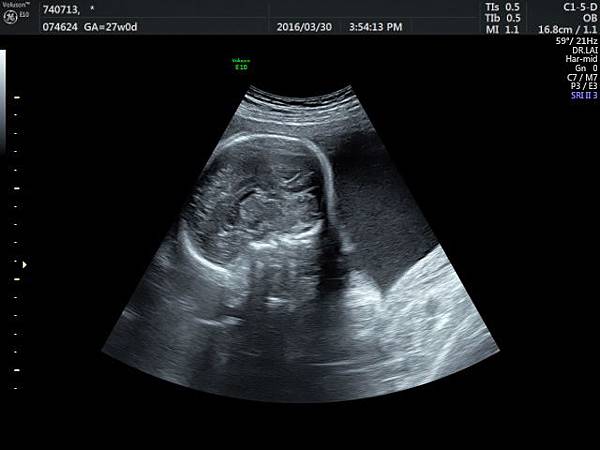

2016年8月4日在執行胎兒高層次超音波檢查時,我發現胎兒腦部的CSP(cavum septum pellucidum)很不清楚(附圖1~4),遇到這種情況,需要仔細評估胎兒腦部的駢胝體,因為CSP的天花板是駢胝體,CSP不明顯時,要合理的懷疑駢胝體沒有發育,或駢胝體下方有長東西(例如lipoma),駢胝體是連接左右大腦的神經纖維所組成。

檢查胎兒駢胝體是有技巧的,需要兩個切面:

1. 矢狀切面(sagittal plane):駢胝體呈現類似三明治的中間黑色部分,上面一層薄薄白色的區域是callosum sulcus,打上flow可以看到pericallosum artery在駢胝體上面的周圍,pericallosum artery來源是前腦動脈,參考附圖 6~10,三明治下面白白的部分是和CSP做比較得到的,如果這一層長lipoma(附圖 5),CSP很可能看不到。